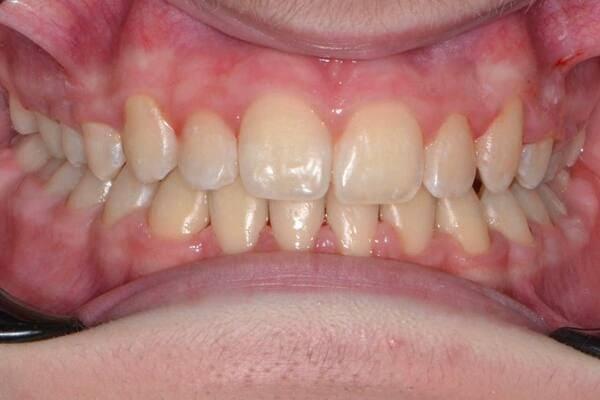

Підлітковий вік — це вирішальний час для остаточного формування прикусу та естетики обличчя. Це ідеальний період для ортодонтичних маніпуляцій, адже саме зараз можна досягти максимального результату з мінімальними зусиллями.

Кісткова тканина в підлітковому віці ще є податливою, що дозволяє досягти чудових результатів значно швидше та з меншим дискомфортом, ніж у дорослих. Нерідко результати, досягнуті в цьому віці, неможливо отримати в дорослому без складних хірургічних втручань.

Наш ортодонт спеціалізується на роботі з підлітками та володіє різними техніками та інструментами для корекції прикусу:

ми використовуємо різні види брекетів — металеві, керамічні, самолігуючі. Це дозволяє індивідуально підібрати систему, яка буде найефективнішою та найкомфортнішою для вашої дитини.

для тих, хто шукає більш естетичне та комфортне рішення, ми пропонуємо лікування за допомогою прозорих елайнерів. Вони дозволяють гармонізувати прикус, залишаючись майже непомітними.